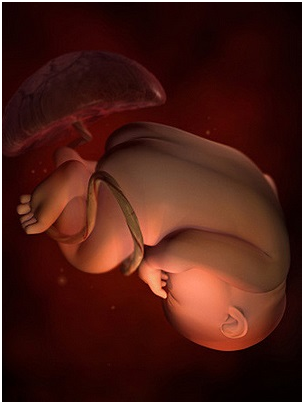

怀孕第32周这个时候,你一定要坚持每两周一次的体检,检查时要注意脐带的扭转情况。最近你可能会...

怀孕第32周这个时候,你一定要坚持每两周一次的体检,检查时要注意脐带的扭转情况。最近你可能会... -